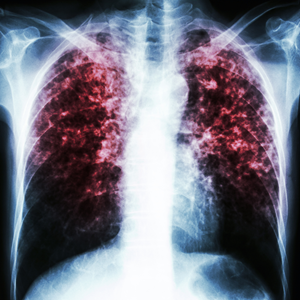

Untreated mould poses serious health risks to tenants. Mould spores can trigger allergic reactions, respiratory issues, and exacerbate asthma symptoms. Prolonged exposure may lead to more severe health conditions, particularly in vulnerable populations such as children, elderly individuals, and those with compromised immune systems.